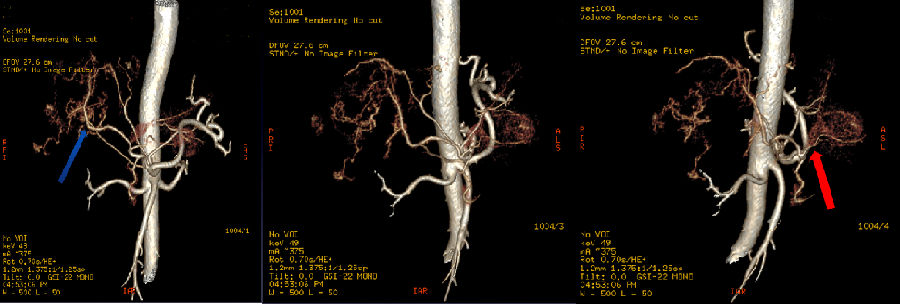

4、血管重建,使用49keV图像观察,显示左右叶病灶丰富的血供情况

图中红、蓝箭头显示肝左右叶病灶分别来源于肝左右动脉